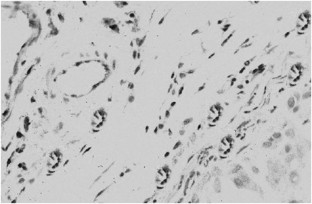

Materials and Methods: We retrospectively analyzed the records on 126 prostate cancer samples from patients treated at our University Hospital from 1995 to 2002. The 72 patients with clinically localized disease (group 1) had undergone radical prostatectomy. Another 54 patients (group 2) had metastatic androgen-independent disease. Archived material relating to the subjects was then immunostained for bcl-2, COX-2 and CD-31, using an anti-bcl-2 monoclonal primary antibody, an anti-COX-2 polyclonal rabbit antibody and an anti-CD-31 monoclonal mouse antibody to evaluate neoangiogenesis (MVD, microvessel density).

Results: We found that bcl-2, COX-2 and MVD expression increased from group 1 to group 2. The intergroup difference was significant only for high MVD (P<0.05). On the other hand, high MVD, high bcl-2 and high COX-2 expression was correlated with a higher PSA level (P<0.01), whereas only a high MVD was also related with Gleason score (P<0.05). We used univariate analysis to evaluate the prognostic impact of biologic and clinico-pathologic parameters on the disease-free-survival of 72 patients treated by radical prostatectomy. A total of 30 patients (41.6%) experienced biochemical relapse; bcl-2, COX-2 and MVD significantly correlated with disease relapse in these patients. In fact, we observed disease relapse in 24/45 (53%) with high bcl-2 expression, in 15/21 (71%) with a high MVD count and finally, in 30/58 (52%) with high COX-2 expression. Finally, PSA value and Gleason score were the only two biologic markers significantly associated to disease relapse in a multivariate analysis.